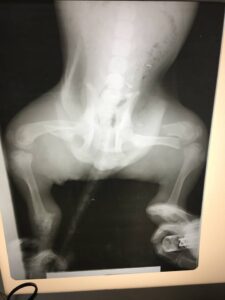

Operationsfotos

Von unserem Patienten (siehe vorletzten Bericht) haben wir hier einige Fotos der erfolgten, erfolgreichen Operation: